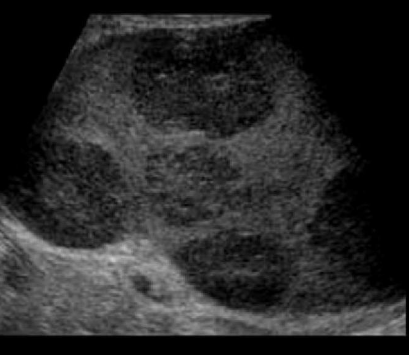

Identify this image.

Splenic hemangioma